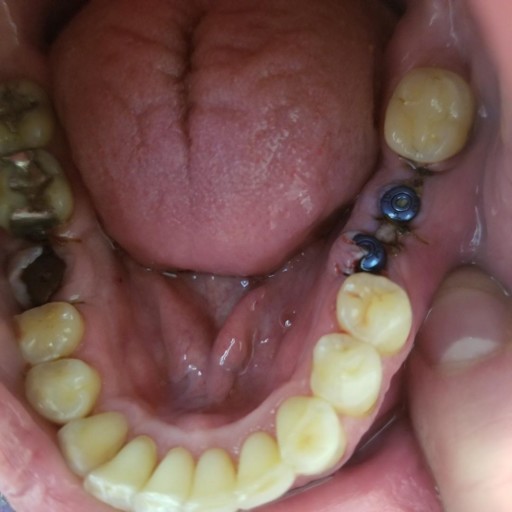

Abutment and crow fell out

Last night my abutment, which is posteriorly located, right side, fell out along with the crown (still intact and attached as one unit). I attempted to re-screw the unit but failed and now the implant site is exposed. At first it seemed that the unit was screwed on but it quickly became loose again. It has been a few weeks since I felt that the crown was loosed but I was not sure what was happening. I will not be able to see my dentist until a month from now. I am worried that I am at risk for infection. Should I and if so what is the likelihood of infection. What can I do in the meantime to minimize that risk until I can see the dentist? I read online that it is quite likely I will need a new abutment and crown. I am wondering if I should even bother with the restoration procedure if especially there is no risk of infection (...minus the lengthening of the upper tooth). I would hate to go through the whole procedure again. Right now I feel no pain, there is no redness or swelling at the site. The only time I feel somewhat a dull, slightly throbbing pain is when I try to screw the abutment back onto the implant.